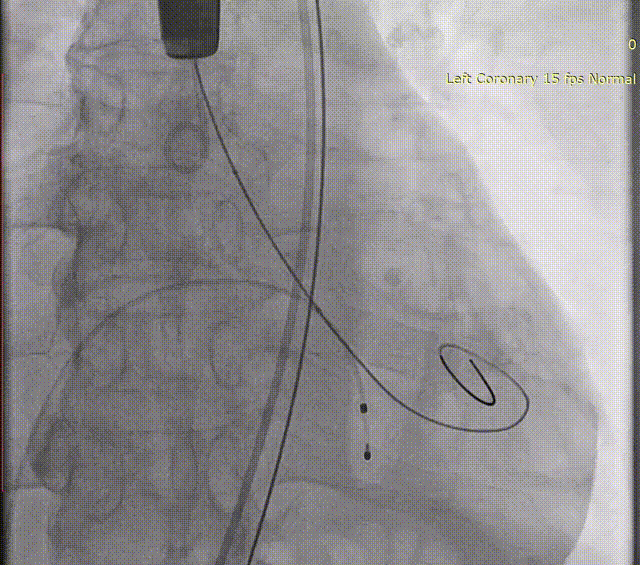

LAAC手术过程

TAVR手术完成后,在TEE指导下,白明教授顺利偏下偏后完成了房间隔穿刺,同时TEE再次检查左心耳开口19-20mm。DSA造影观察与术前CTA多平面重建结果吻合,左心耳浅鸡翅型,测量左心耳开口24.9mm深度22mm。经过充分讨论和手术策略分析,决定为患者使用WATCHMAN FLX™ 31mm封堵器进行左心耳封堵。WATCHMAN FLX™器械由于和WATCHMAN设计的不同,导引鞘不需要进入左心耳远端,即可安全展开封堵器。术中白明教授送入WATCHAMN FLX™ 31mm输送系统后,退鞘形成FLX BALL,后采用进退结合法,“毛毛虫”式展开封堵器。造影观察封堵效果理想,牵拉试验稳定,在TEE上观察封堵器微露肩,压缩比21%,各角度无残余分流,最终释放左心耳封堵器。术后观察患者心包积液相比术前无变化,生命体征平稳,一站式手术顺利完成。